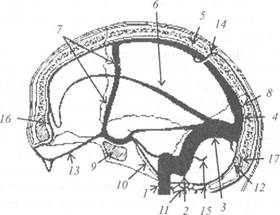

Анатомические изображения срединной сагиттальной линии черепа